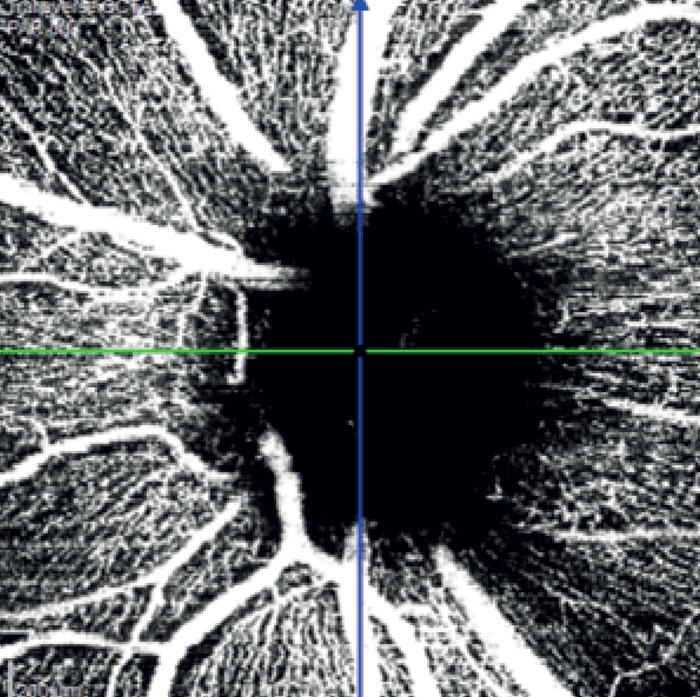

In the left eye – which had a mild inferotemporal RNFL thinning and a normal visual field – SPECTRALIS OCT Angiography revealed a wedge defect and corresponding profound capillary dropout around the optic nerve head (see Figure 8). This corresponded to capillary dropout in the inferior macula (see Figure 9).